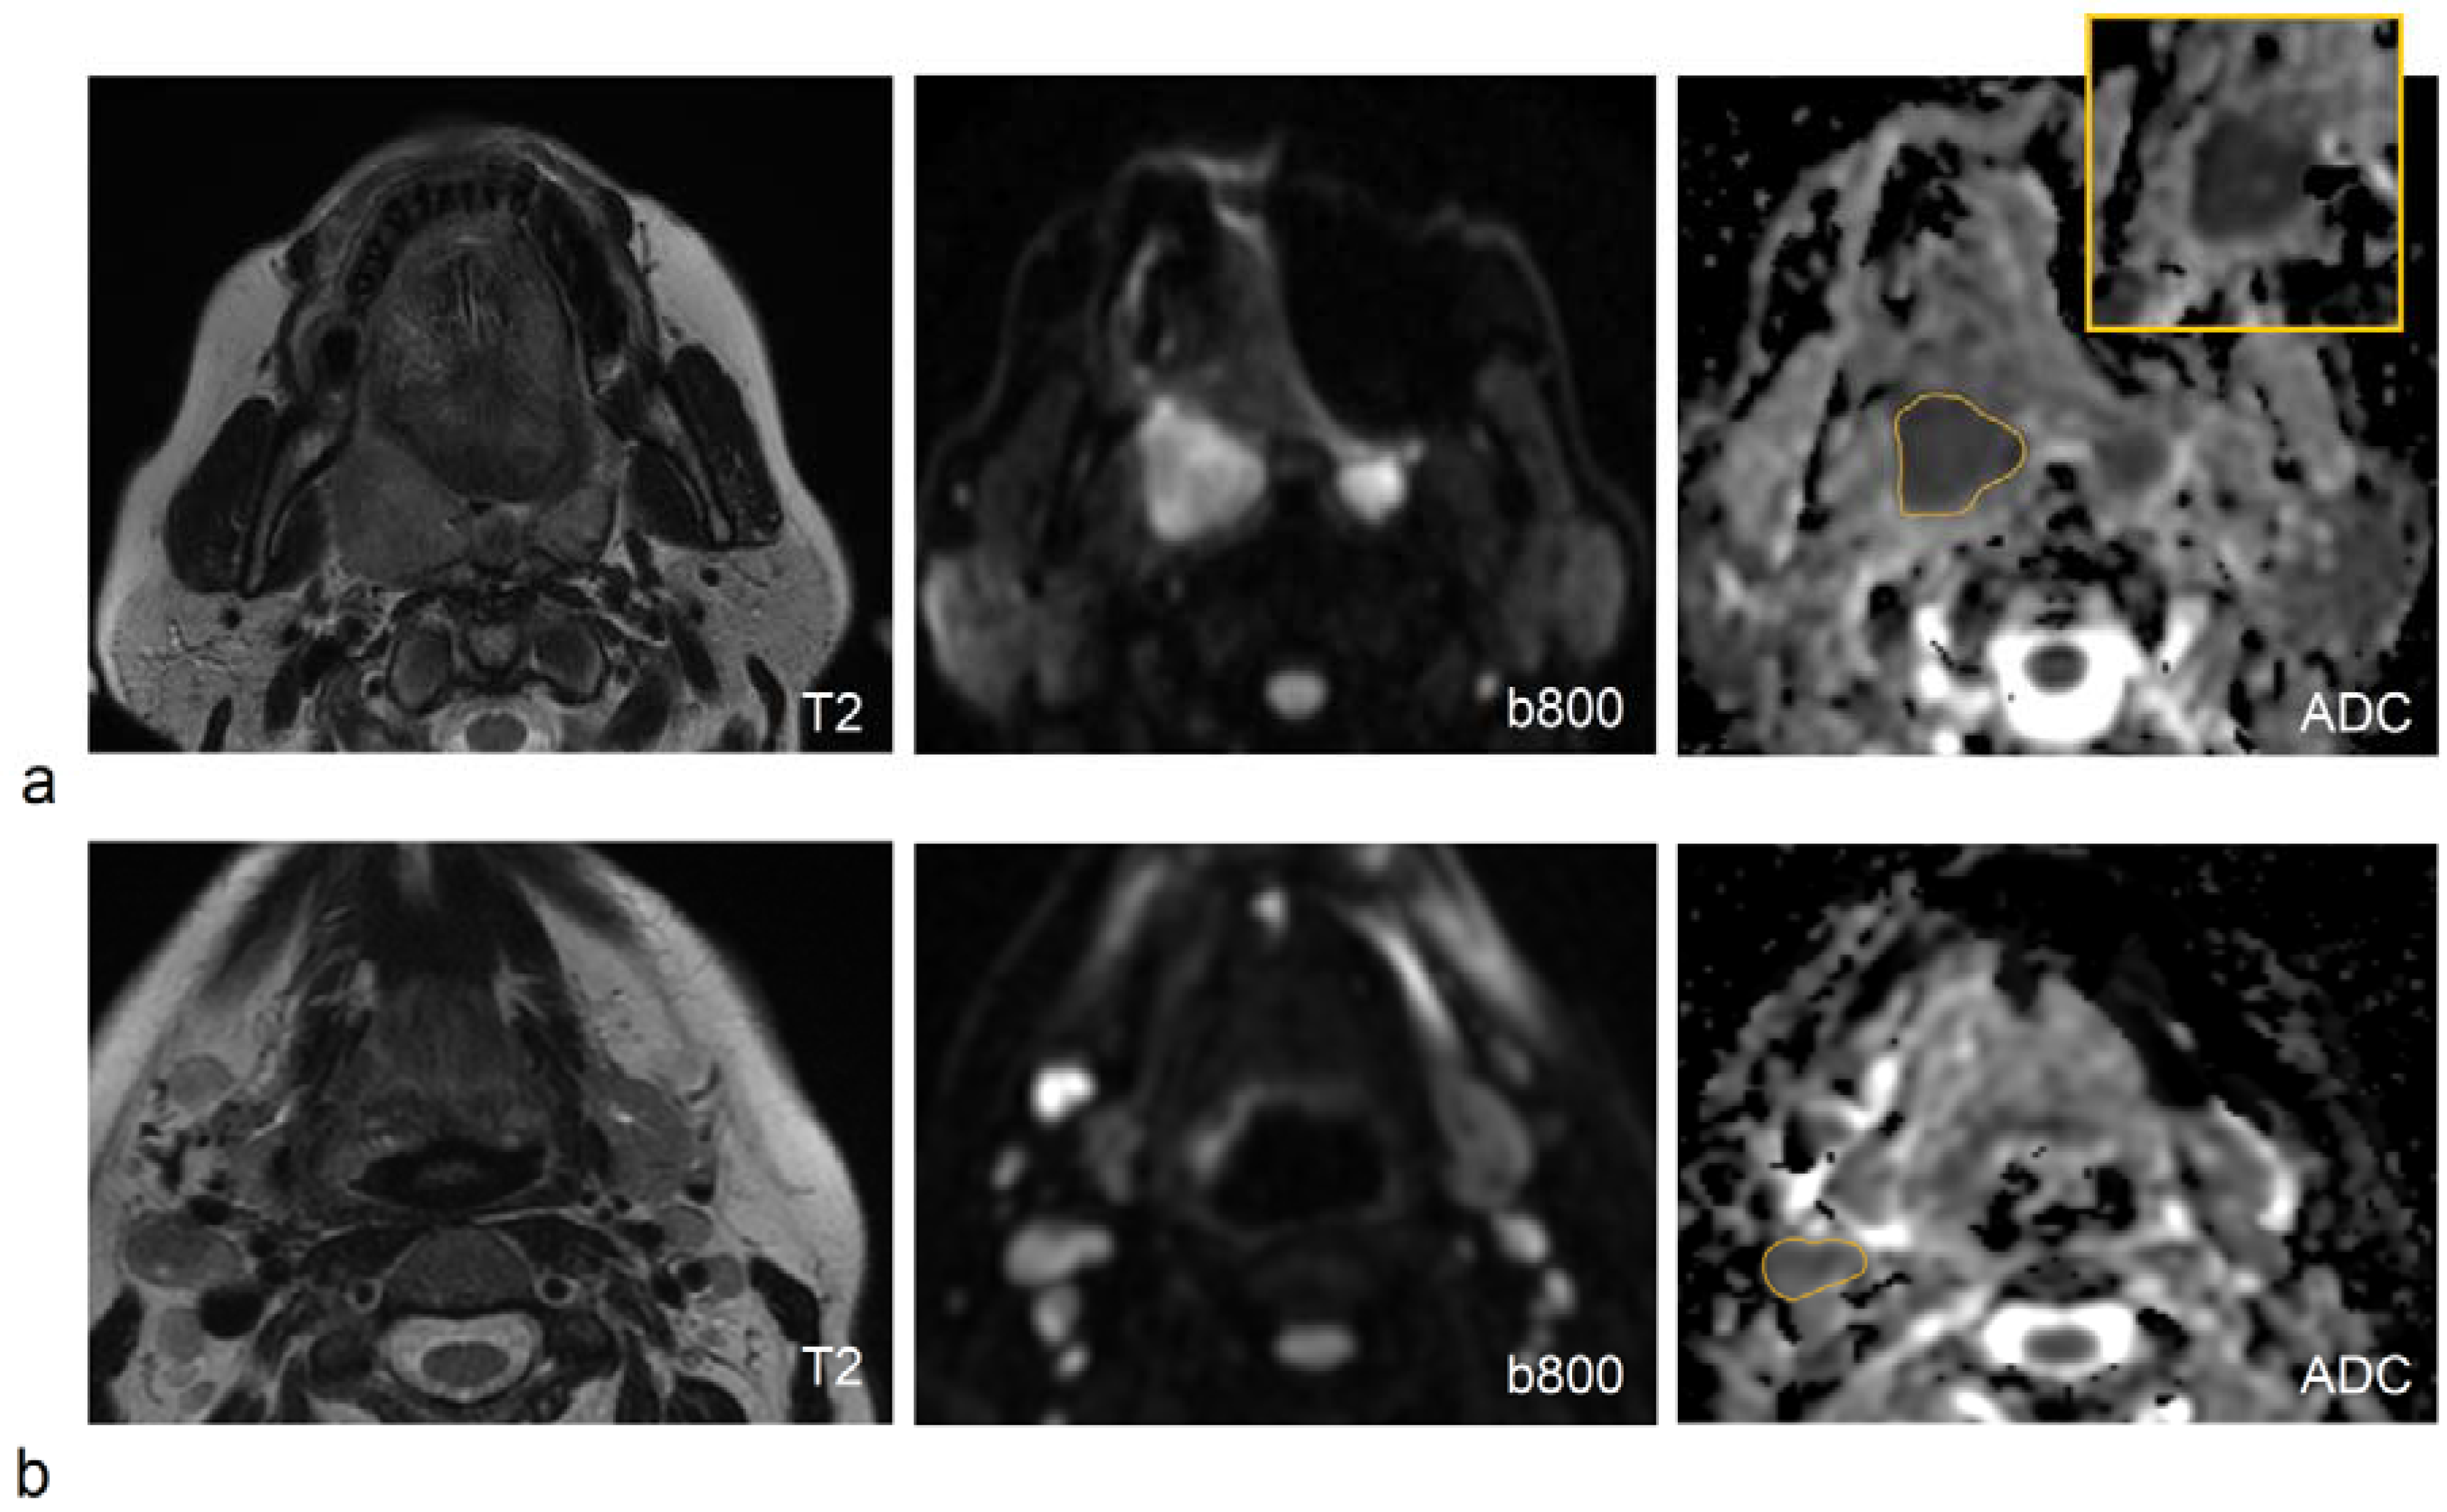

- Ravanelli, M.; Grammatica, A.; Tononcelli, E.; Morello, R.; Leali, M.; Battocchio, S.; Agazzi, G.M.; Buglione di Monale, E.; Bastia, M.; Maroldi, R.; et al. Correlation between Human Papillomavirus Status and Quantitative MR Imaging Parameters including Diffusion-Weighted Imaging and Texture Features in Oropharyngeal Carcinoma. AJNR. Am. J. Neuroradiol. 2018, 39, 1878–1883. [Google Scholar] [CrossRef]

- Vidiri, A.; Marzi, S.; Gangemi, E.; Benevolo, M.; Rollo, F.; Farneti, A.; Marucci, L.; Spasiano, F.; Sperati, F.; Di Giuliano, F.; et al. Intravoxel incoherent motion diffusion-weighted imaging for oropharyngeal squamous cell carcinoma: Correlation with human papillomavirus Status. Eur. J. Radiol. 2019, 119, 108640. [Google Scholar] [CrossRef]